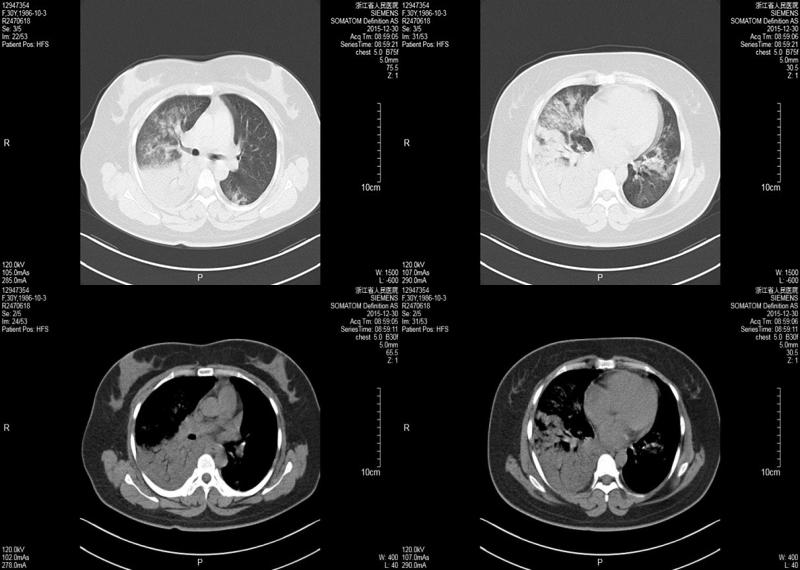

患者入院后持续高热,呼吸急促,复查血常规+CRP:WBC 2.05×109/L,L 0.66×109/L,PLT 62×109/L,CRP 68.2mg/L;ALT 29U/L,AST 116U/L,Cr 60.8μmol/L,LDH 1017U/L,CK 2749U/L;PCT 0.41ng/ml;血气:PH 7.414,PO254.90mmHg,PCO237.3mmHg,Lac 1.2mmol/L。肺部CT:双肺散在斑片样、絮样密度增高影,右侧大量胸腔积液(图2)。

(图2 肺CT检查)